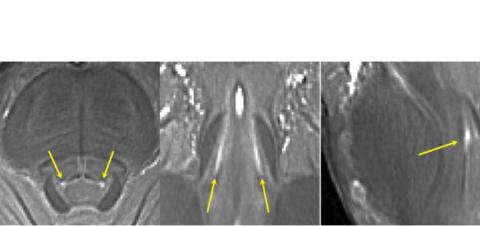

L'étude s'est concentrée sur le le locus coeruleus, producteur de noradrénaline : l’auteur principal, le Pr James Rowe du Département des neurosciences cliniques de l'Université de Cambridge commente : « La noradrénaline est très importante pour le fonctionnement du cerveau. Tout l'approvisionnement de notre cerveau provient d'une minuscule région à l'arrière du cerveau appelée le locus coeruleus (Voir visuel), une zone cérébrale très fine et dissimulée à la base même du cerveau dans le tronc cérébral". Son équipe avait déjà montré, lors d’une précédente étude, que certains patients atteints de PSP perdent jusqu'à 90 % du locus coeruleus producteur de noradrénaline.

Mais comment étudier cette zone minuscule ? Alors que la plupart des scanners IRM ont tendance à être « 3T » ou moins et ne permettent pas de visualiser avec suffisamment de précision le locus coeruleus, les scanners 7T, qui ont des champs magnétiques ultra-puissants, peuvent fournir une résolution de la taille d'un grain de sable. Ces scanners ont permis à l'équipe d'examiner le locus coeruleus et de confirmer que :